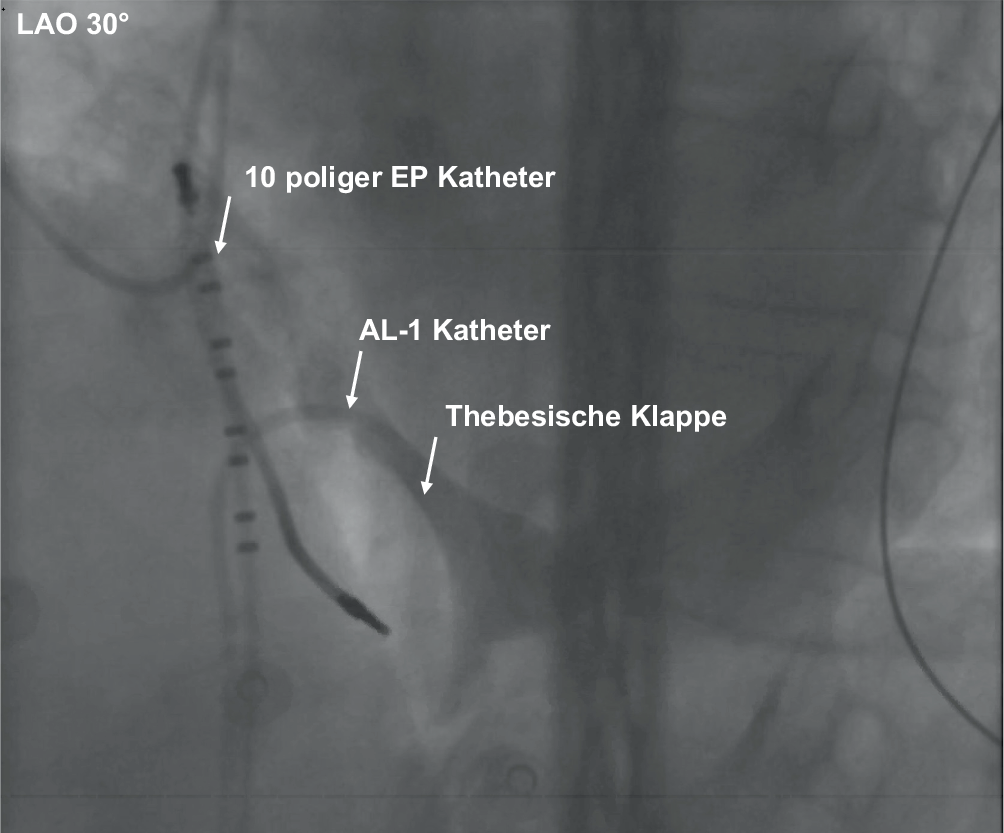

Sobald das CS-Ostium lokalisiert wurde, kann eine kleine Menge Kontrastmittel dabei helfen, den Verlauf des Koronarsinus darzustellen. Das CS-Ostium ist bei einzelnen Patienten aufgrund einer ostialen Venenklappe kaum sondierbar (Thebesische Klappe). Diese Klappe ist bei den meisten Patienten klein angelegt, kann den Zugang zum CS jedoch auch subtotal verschließen. Sie kann von kranial oder von kaudal mit einem steuerbaren EP-Katheter oder einem 6‑French-Amplatz-Links-Katheter (1 oder 2) zur Seite gedrängt und dann nach Darstellung mit dem CS-Guide passiert werden (Abb. 4). Der Guide wird vorsichtig bis zur mittleren lateralen Region vorgeschoben, wobei darauf geachtet wird, Seitäste oder die atriale Vene des linken Atriums (Marshall-Vene) zu vermeiden. An diesem Punkt kann die Drehung des Katheters oder die Verwendung eines hydrophilen Drahtes innerhalb des Katheters den Vorschub desselben erleichtern. Insbesondere im proximalen Drittel ist der CS anatomisch bedingt vulnerabel und dissektions- bzw. perforationsgefährdet.

Abb. 4

Thebesische Klappe, die über einen femoralen Zugang mittels AL-1-Katheter dargestellt wurde. Ebenfalls einliegend 10-poliger Inquiry-Katheter der Firma Abbott